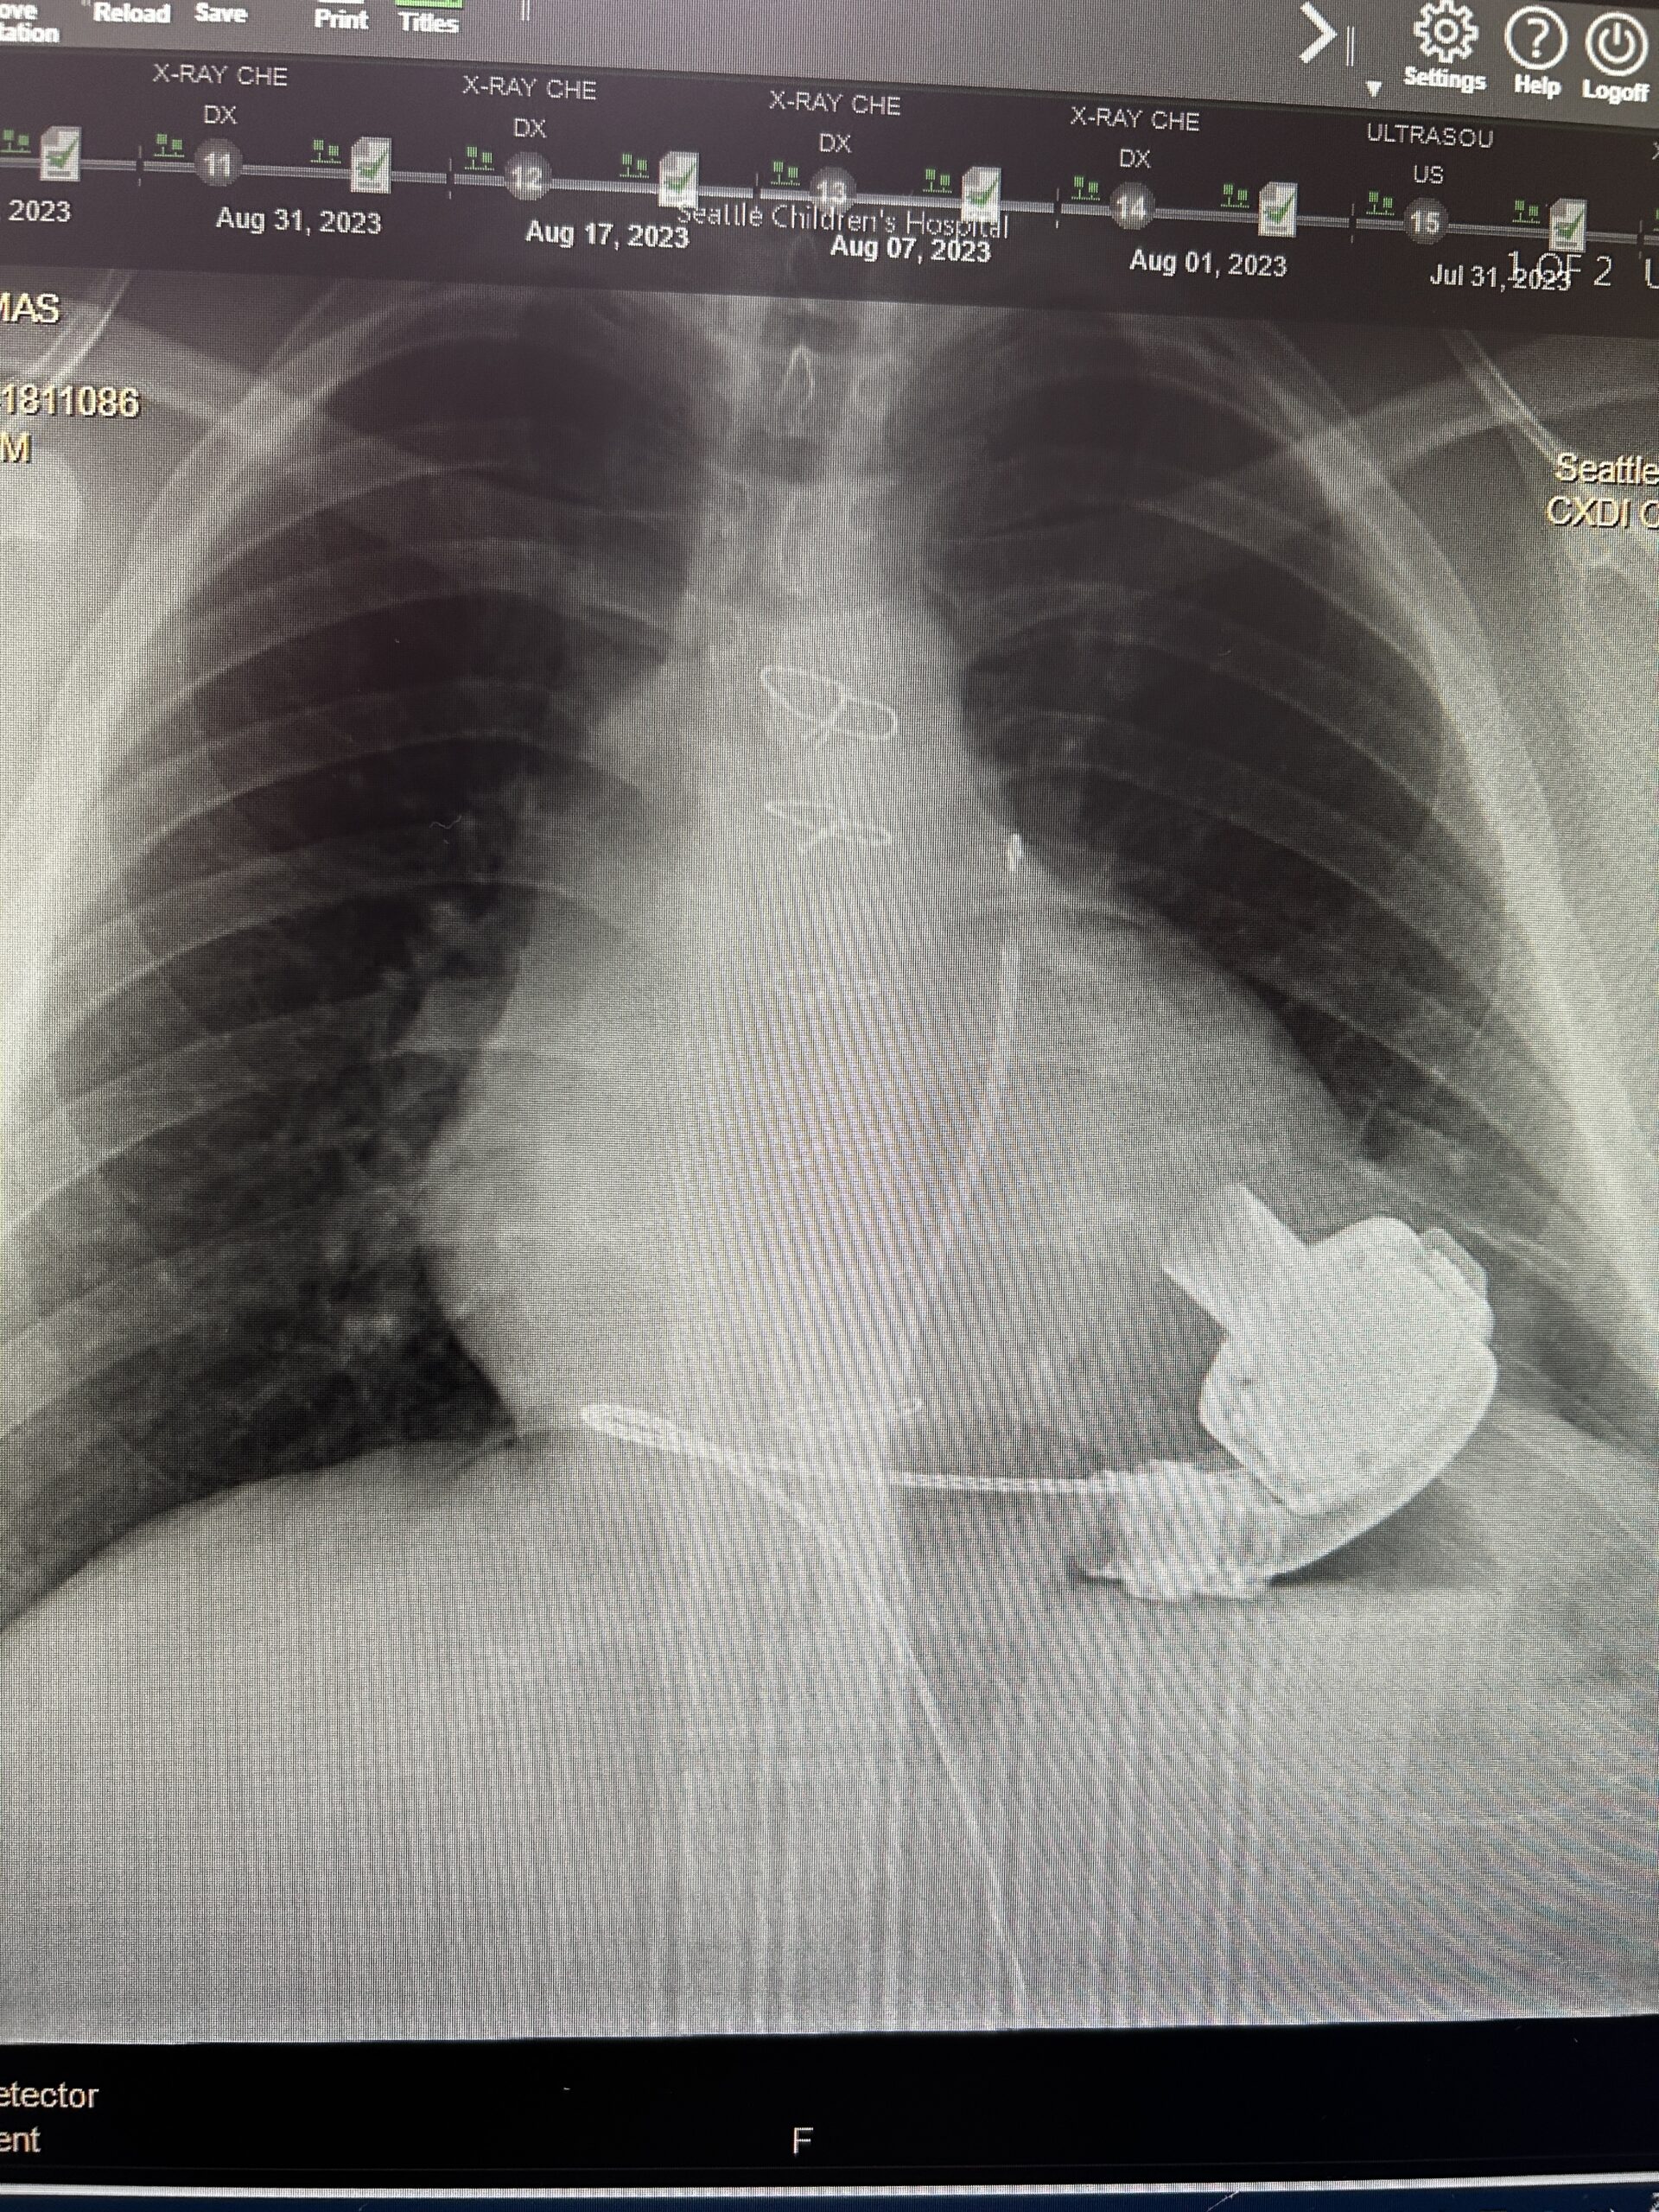

Today, we finished what was supposed to be a short appointment to put some silver nitrate on a very irritated area at Josiah’s driveline’s entry point. Hopefully, this treatment will help an area that has been bothering him for a couple of months.

It turns out that when a heart that is too small is placed where a larger heart was, there can be major issues leading to yet another heart failure. So they double-checked all the measurements of his heart and the donor’s heart, just in case. They had to pass.

Thankfully, Josiah is stable enough that he can wait for the right heart. (I’ll share more in another post about the many variables that determine where a patient falls on the list.)